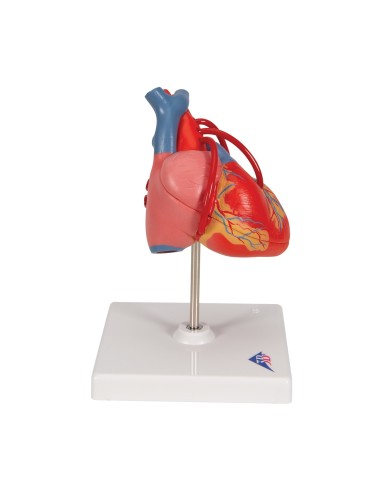

NON PIU' IN PRODUZIONE

Su tavola, con supporto e istruzioni per l'insegnamento. Con colorante rosso e siringa di riempimento.